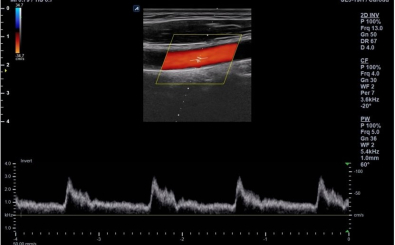

Carotid